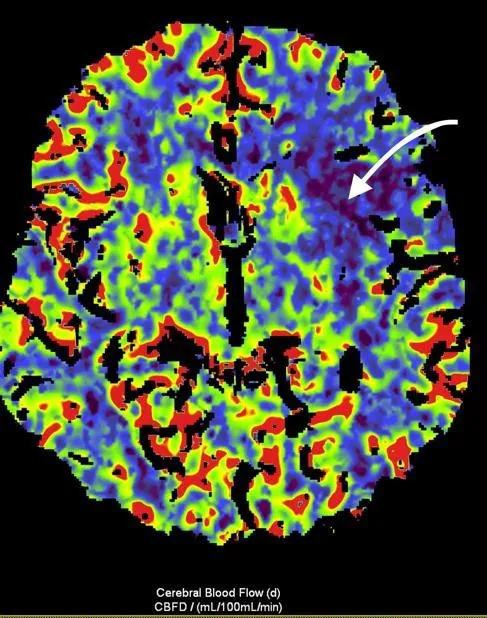

Рисунок 3. МСКТ-перфузійні зображення пацієнта Д.

Представлені карти МСКТ-перфузійних зображень демонструють зони дуже низької перфузії при CBV (a) та CBF (b), що відповідають ядру інфаркту (біла стрілка), та велику зону, що відповідаї пенумбрі (зелений овал) при TMax-map (c).

Відповідно до результатів нейровізуалізації та візуалізації церебральних артерій у пацієнта Д. був діагностований ішемічний інсульт, що обумовлений оклюзією великої мозкової артерії (лівої внутрішньої сонної артерії [ВСА] та лівої середньої мозкової артерії [СМА]). Згідно з результатами автоматичного обчислення, на момент дослідження об’єм ядра інфаркту у пацієнта Д. склав 24,6 см3, а об’єм зони пенумбри – 47,9 см3. Отже, об’єм зони пенумбри становив 194,7% об’єму ядра (співвідношення пенумбри та інфаркта майже 2:1). Зважаючи на це, ситуація була обговорена з лікарем-нейрохірургом С. В. Конотопчиком і о 14:45 пацієнт бригадою НМД «Оберіг» був доправлений у ДУ «НПЦ Ендоваскулярної нейрорентгенохірургії НАМН України» та спрямований одразу до операційної.